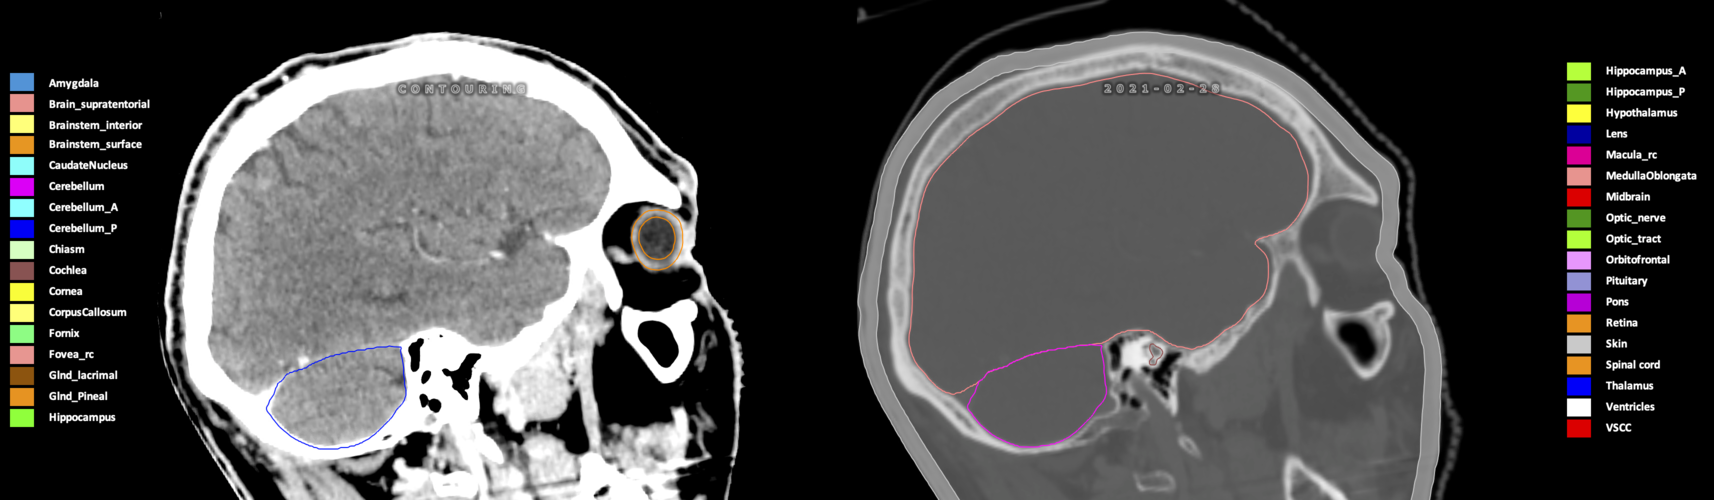

Three-dimensional delineation of the 25 consensus OARs for neuro-oncology are shown on CT (WW/WL 120/40, 3000/600), 3T MR images, (T1Gd, T2FLAIR 1mm) and 7T MR (MP2RAGE 0.7 mm). All are presented in transversal, sagittal and coronal view.

Included are all OARs known to be relevant for radiation-induced toxicity in neuro-oncology: brain, brainstem (midbrain, pons, medulla oblongata), chiasm, cerebellum (anterior & posterior), cochlea, cornea, hippocampus (anterior & posterior), hypothalamus, lens, lacrimal gland, optic nerve, pituitary, skin, and vestibular & semicircular canals. To further facilitate research on cognition, vision and radiological changes after irradiation of the brain, potential clinically-relevant OARs are included: amygdala, caudate nucleus, cerebellum (anterior & posterior), corpus callosum, fornix, macula, optic tract, orbitofrontal cortex, periventricular space (PVS), pineal gland, and thalamus.